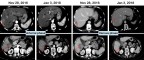

The most impressive finding was that 44% of the patients with Child Pugh B7 treated with Namodenoson were alive at one year compared to 18% in the placebo group. In the overall patient population, among patients who had at least one assessment post baseline, disease control was significant in the Namodenoson group, 26% versus 10% in the control group after four months of treatment, P value 0.013. Among the other positive findings that were presented is the 9% partial response in the Namodenoson treated group vs. 0% in the placebo group. An example of a patient demonstrating an excellent tumor shrinkage was presented. (See Figure 2)